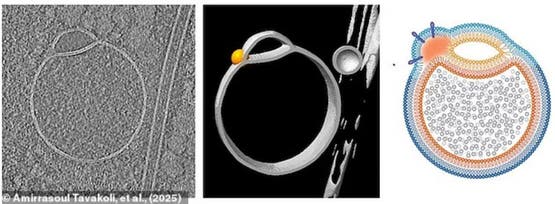

اكتشف العلماء بنية جديدة وغامضة كامنة داخل كل خلية بشرية، ويبلغ قطر هذه البُنى الصغيرة، التي أُطلق عليها اسم الهيميفيوسومات (hemifusomes)، ما بين 200 إلى 400 نانومتر فقط، أي ما يعادل نحو 500 مرة أقل من سُمك شعرة الإنسان.

نظرًا لصغر حجم الهيميفيوسومات الشديد، احتاج الباحثون إلى معدات فائقة الحساسية لرصدها. استخدم الفريق البحثي تقنية تُعرف باسم التصوير المقطعي الإلكتروني بالتبريد (cryo-electron tomography)، حيث تُجمّد العينات بسرعة إلى حوالي 150 درجة مئوية تحت الصفر، ثم تُقطّع إلى شرائح دقيقة جدًا.

بعد ذلك، التقط العلماء عددًا كبيرًا من الصور باستخدام مجهر إلكتروني يعمل بالإلكترونات بدلًا من الضوء المرئي. سمحت لهم هذه التقنية بمشاهدة البُنى الصغيرة للغاية كما لو كانت داخل خلية حية، عبر “تجميدها في الزمن”، بدلًا من إتلافها خلال محاولات الحفظ التقليدية.

يعتقد الباحثون أن الهيميفيوسومات تُنتج الحويصلات، وهي أكياس صغيرة تعمل كـ”أوعية خلط” داخل الخلية، كما أنها تُشكّل بُنى تتكون من عدد كبير من هذه الحويصلات..